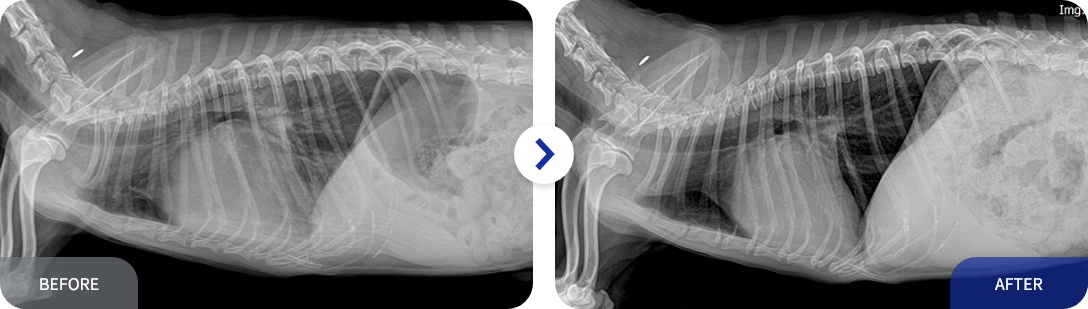

진료 및 치료 사례

• 신장- Sub시술

• 심장 - 폐수종 치료

• 호흡기 - 폐렴 치료